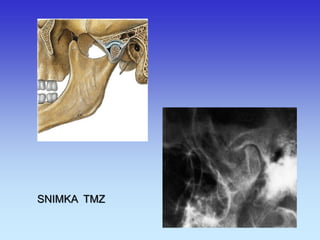

TEMPOROMANDIBULARNI ZGLOBOVI

SNIMKA TMZ